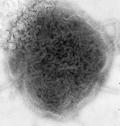

Categories: Mumps virus